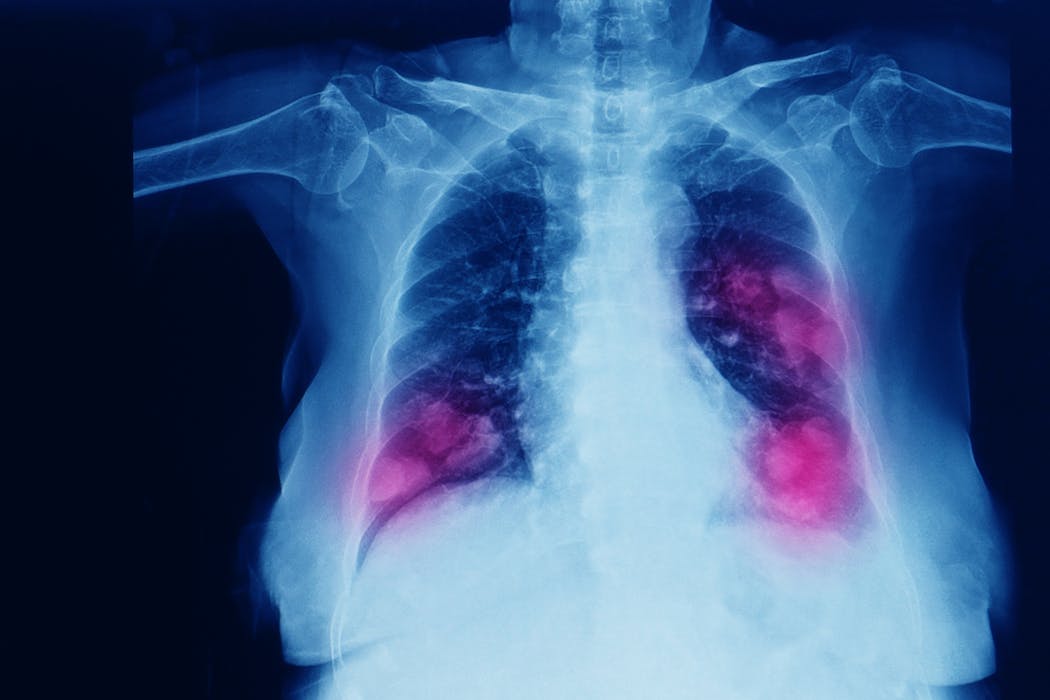

El paso del tiempo lo cambia casi todo menos la principal causa de cáncer en el mundo, que en las últimas décadas ha sido el cáncer de pulmón. Solo en España se diagnostican más de 30 000 casos cada año, y la supervivencia a cinco años apenas alcanza el 20 %. Parte del problema es que los tumores suelen detectarse tarde y que los tratamientos, incluso los más novedosos, acaban perdiendo eficacia.